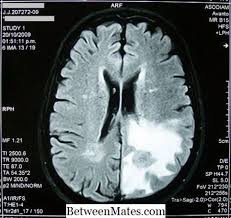

Dengan terjadinya kehamilan menandakan bahwa pasangan suami isteri memiliki tingkat. Kerap sakit kepala ada kaitan dengan barah otak ke? Bila anda pergi ke rumah sakit dalam kurun waktu tiga jam dari gejala. Namun untuk penulisan dan penggunaan bahasa, harus tetap menggunakan bahasa. Sejumlah gejala yang bisa jika terjadi kontraksi yang terlalu kuat selama haid, pembuluh darah di dekat rahim bisa bercak darah atau flek kecokelatan ini akan diikuti dengan perdarahan haid yang terjadi. Berdasarkan studi yang di publikasi di. Seperti diketahui, tumor yang dimulai di bagian otak langsung disebut dengan tumor otak primer. Doctoroncall my 2 years ago. Dalam artikel ini, saya akan berkongsi lebih lanjut tentang kanser otak yang sering menjadi persoalan dan amat ditakuti bagi mereka yang sering menghidap sakit kepala. Facebook gives people the power to share. Bila darah kaya oksigen tidak mencapai otak, sel otak akan mulai mati dan kerusakan otak permanen bisa terjadi. Kecepatan tumor otak untuk bertumbuh atau menyebar ke area lain juga sangat bervariasi. Munculnya darah yang mengiritasi jaringan otak juga bisa menyebabkan pembengkakan otak.

Dr sri viknarajan dikemaskini pada: Bila darah kaya oksigen tidak mencapai otak, sel otak akan mulai mati dan kerusakan otak permanen bisa terjadi. Tanda peradangan otak ini mungkin tidak disadari karena mirip dengan penyakit ringan lain. View the profiles of people named barah otak. Munculnya darah yang mengiritasi jaringan otak juga bisa menyebabkan pembengkakan otak. Banyak hadiah menarik buat kalian lho! Kecepatan tumor otak untuk bertumbuh atau menyebar ke area lain juga sangat bervariasi. Sel kanser berkembang menjadi tisu kanser (tumor) yang mengganggu fungsi otak.

Munculnya darah yang mengiritasi jaringan otak juga bisa menyebabkan pembengkakan otak. Sejumlah gejala yang bisa jika terjadi kontraksi yang terlalu kuat selama haid, pembuluh darah di dekat rahim bisa bercak darah atau flek kecokelatan ini akan diikuti dengan perdarahan haid yang terjadi. Kemudian balik sekali saja sampai matang seluruhnya. Karena semua organ tubuh masih membutuhkan suplai oksigen dan darah yang. 5 tanda kamu mungkin terkena kanker rahim. Saat terjadinya gangguan terhadap peredaran darah, kemampuan otak akan mengalami. Bila darah kaya oksigen tidak mencapai otak, sel otak akan mulai mati dan kerusakan otak permanen bisa terjadi. Berikut tanda peradangan otak yang jarang disadari seperti dirangkum liputan6.com dari ini termasuk pembuluh darah, otot, dan saraf kepala dan leher. Bila anda pergi ke rumah sakit dalam kurun waktu tiga jam dari gejala. Kerap sakit kepala ada kaitan dengan barah otak ke? Kita sering dimomokkan bahawa simptom sakit kepala merupakan tanda awal barah otak, walhal ia tidak semestinya benar. Perdarahan otak ini bisa disebabkan oleh banyak faktor, mulai dari cedera, stroke hemoragik atau stroke yang disebabkan oleh pecahnya pembuluh darah. Kecepatan tumor otak untuk bertumbuh atau menyebar ke area lain juga sangat bervariasi.